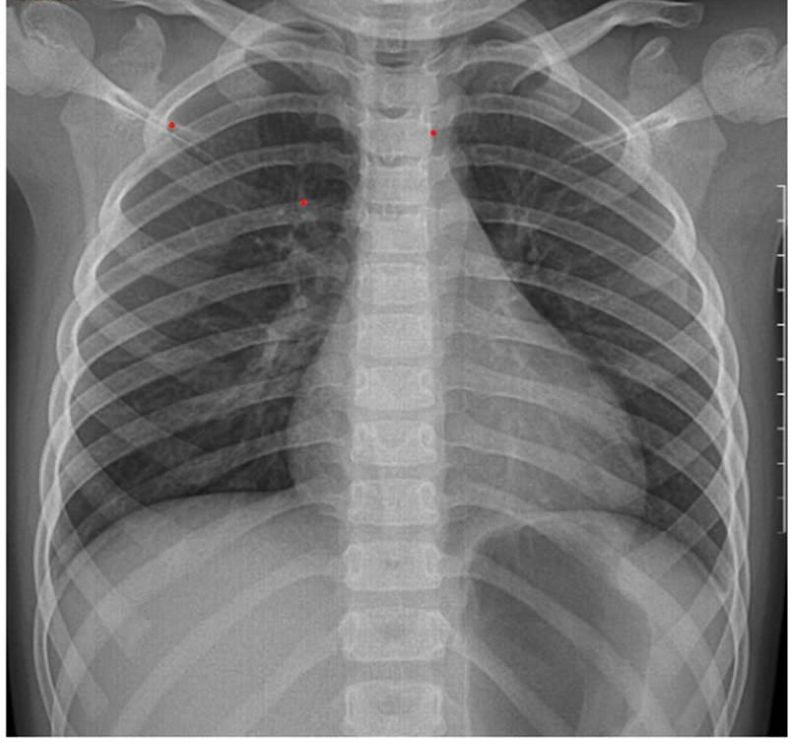

X-quang phổi cho thấy dày nhẹ thành phế quản ở vùng trung tâm và vùng thấp của cả hai phổi, nhưng không có tổn thương nghiêm trọng.